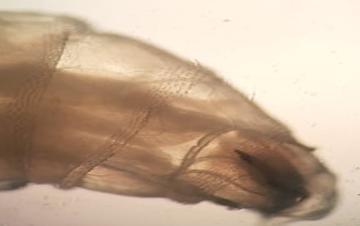

A 60-year-old male patient from Bizerte, was admitted in the Department of Infectious Diseases of the Military Hospital of Tunis on September 2019 for management of diabetic foot wound. The patient had a type 2 diabetes for 28 years at the stage of degenerative complications, hypertension for 4 years, coronary disease and chronic renal failure for two years. Six months ago, he underwent amputation of the 2nd, 3rd and 4th toes of the right foot. After two months, he began the sessions of hyperbaric oxygen therapy (HBOT), during which, a whitish worm mobile, 12mm in length, was observed at the wound (Figure 1).The larvae were collected and transferred to the parasitology department. The species identification was made according to Zumpt criteria. These were L3 stage larvae of Lucilia sericata. The larva was semi-cylindrical with a tapered anterior end containing chitinous buccal hooks (Figure 2). In the posterior end there were respiratory spiracles (Figure 3) containing a narrow peritreme which forms a completely closed ring and surrounds a highly visible button. The spiracular plates had straight and parallel slits. The distance between the inner tubercles on the upper edge of the posterior cavity is approximately equal to that between the middle tubercles.

Figure 2 Anterior end of larva: chitinous buccal hooks.

Figure 3 Posterior end of the larva: Respiratory spiracles.